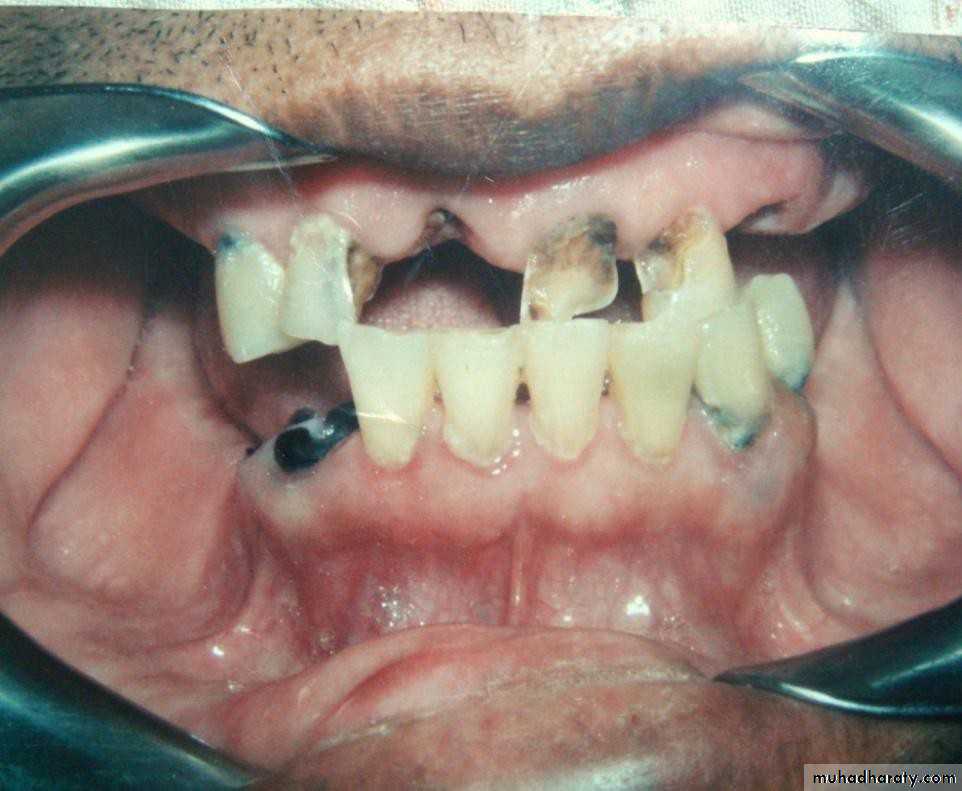

• Gold or metallic cast Copings and telescopic crowns are a method of improving overdenture retention. These

• may be conical crowns (semi- parallel wall) with a friction adaptation at the marginal area of the abutment, or Milled crowns for larger areas and parallel surfaces.

• Friction retention is more commonly used in exclusively tooth-supported overdentures

that are not supported by soft

tissue.